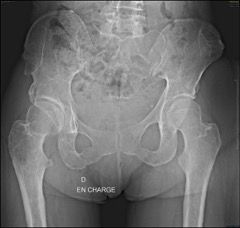

Neck-shaft angle

The “round the corner” technique of stem implantation involves following the medial femoral cortex, meaning that the physiological medial curvature of each patient can be restored. The main condition is to retain sufficient femoral neck to guide the insertion path of the compactors preparing the way for the stem. This means it is important to uphold the principle of not cutting the femoral neck too extensively, above all in coxa vara hips. The cut is therefore often made higher than it would be for a standard stem, usually between 15 and 25 mm above the lesser trochanter. It is essential to plan the surgical intervention thoroughly in order to obtain the desired result. With this type of stem and by following this technical principle, the prosthetic hip is restored to a neck-shaft angle that is similar to that of the native hip.

Femoral offset

The anatomical positioning of short stems along the medial cortex will also allow for restoration of femoral offset. Most of the time this is an advantage over straight stems even in “standard” hips, as it is in some specific cases.

Hips in coxa vara sometimes present a very significant femoral offset which may be prove to be difficult to restore using standard stems. In this case, a varus-tilted or lateralized stem should be used and this will require a very low femoral cut, often with loss of residual femoral offset and a risk of lengthening the lower limb. Positioning a straight cementless stem in varus runs the risk of trajectory error and femoral pain. If a modular neck implant is chosen, the increased lever arm results in significant pressures on the modular neck and neck-head junction with risks that are already known. Finally, even with a cemented stem, positioning it in varus will increase the pressures on the bone-cement interface, with a risk of early loosening. With calcar-guided short stems, the stem will follow the medial cortex of the neck (which will have been cut high), naturally finding a varus tilt and making it possible to reproduce even very significant offsets (Figs 4 and 5).